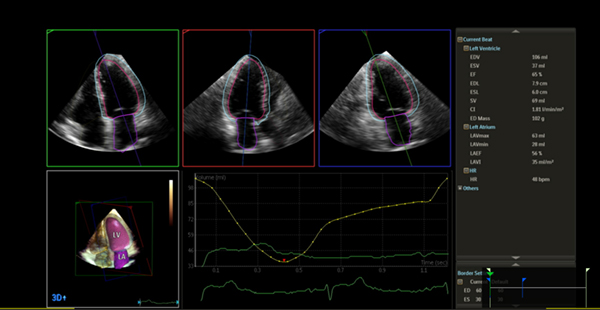

Dynamic HeartModel に対応

EPIQ CVx Transcend Plus の使用可能な Dynamic HeartModel がAffiniti CVx Transcend Plusでも対応となりました。 LVやLAの境界の動きや,LVとLAのIndexなど,左心機能,LV壁運動,および心周期におけるLVとLAのボリューム変化の連動性を総合的に把握できます。